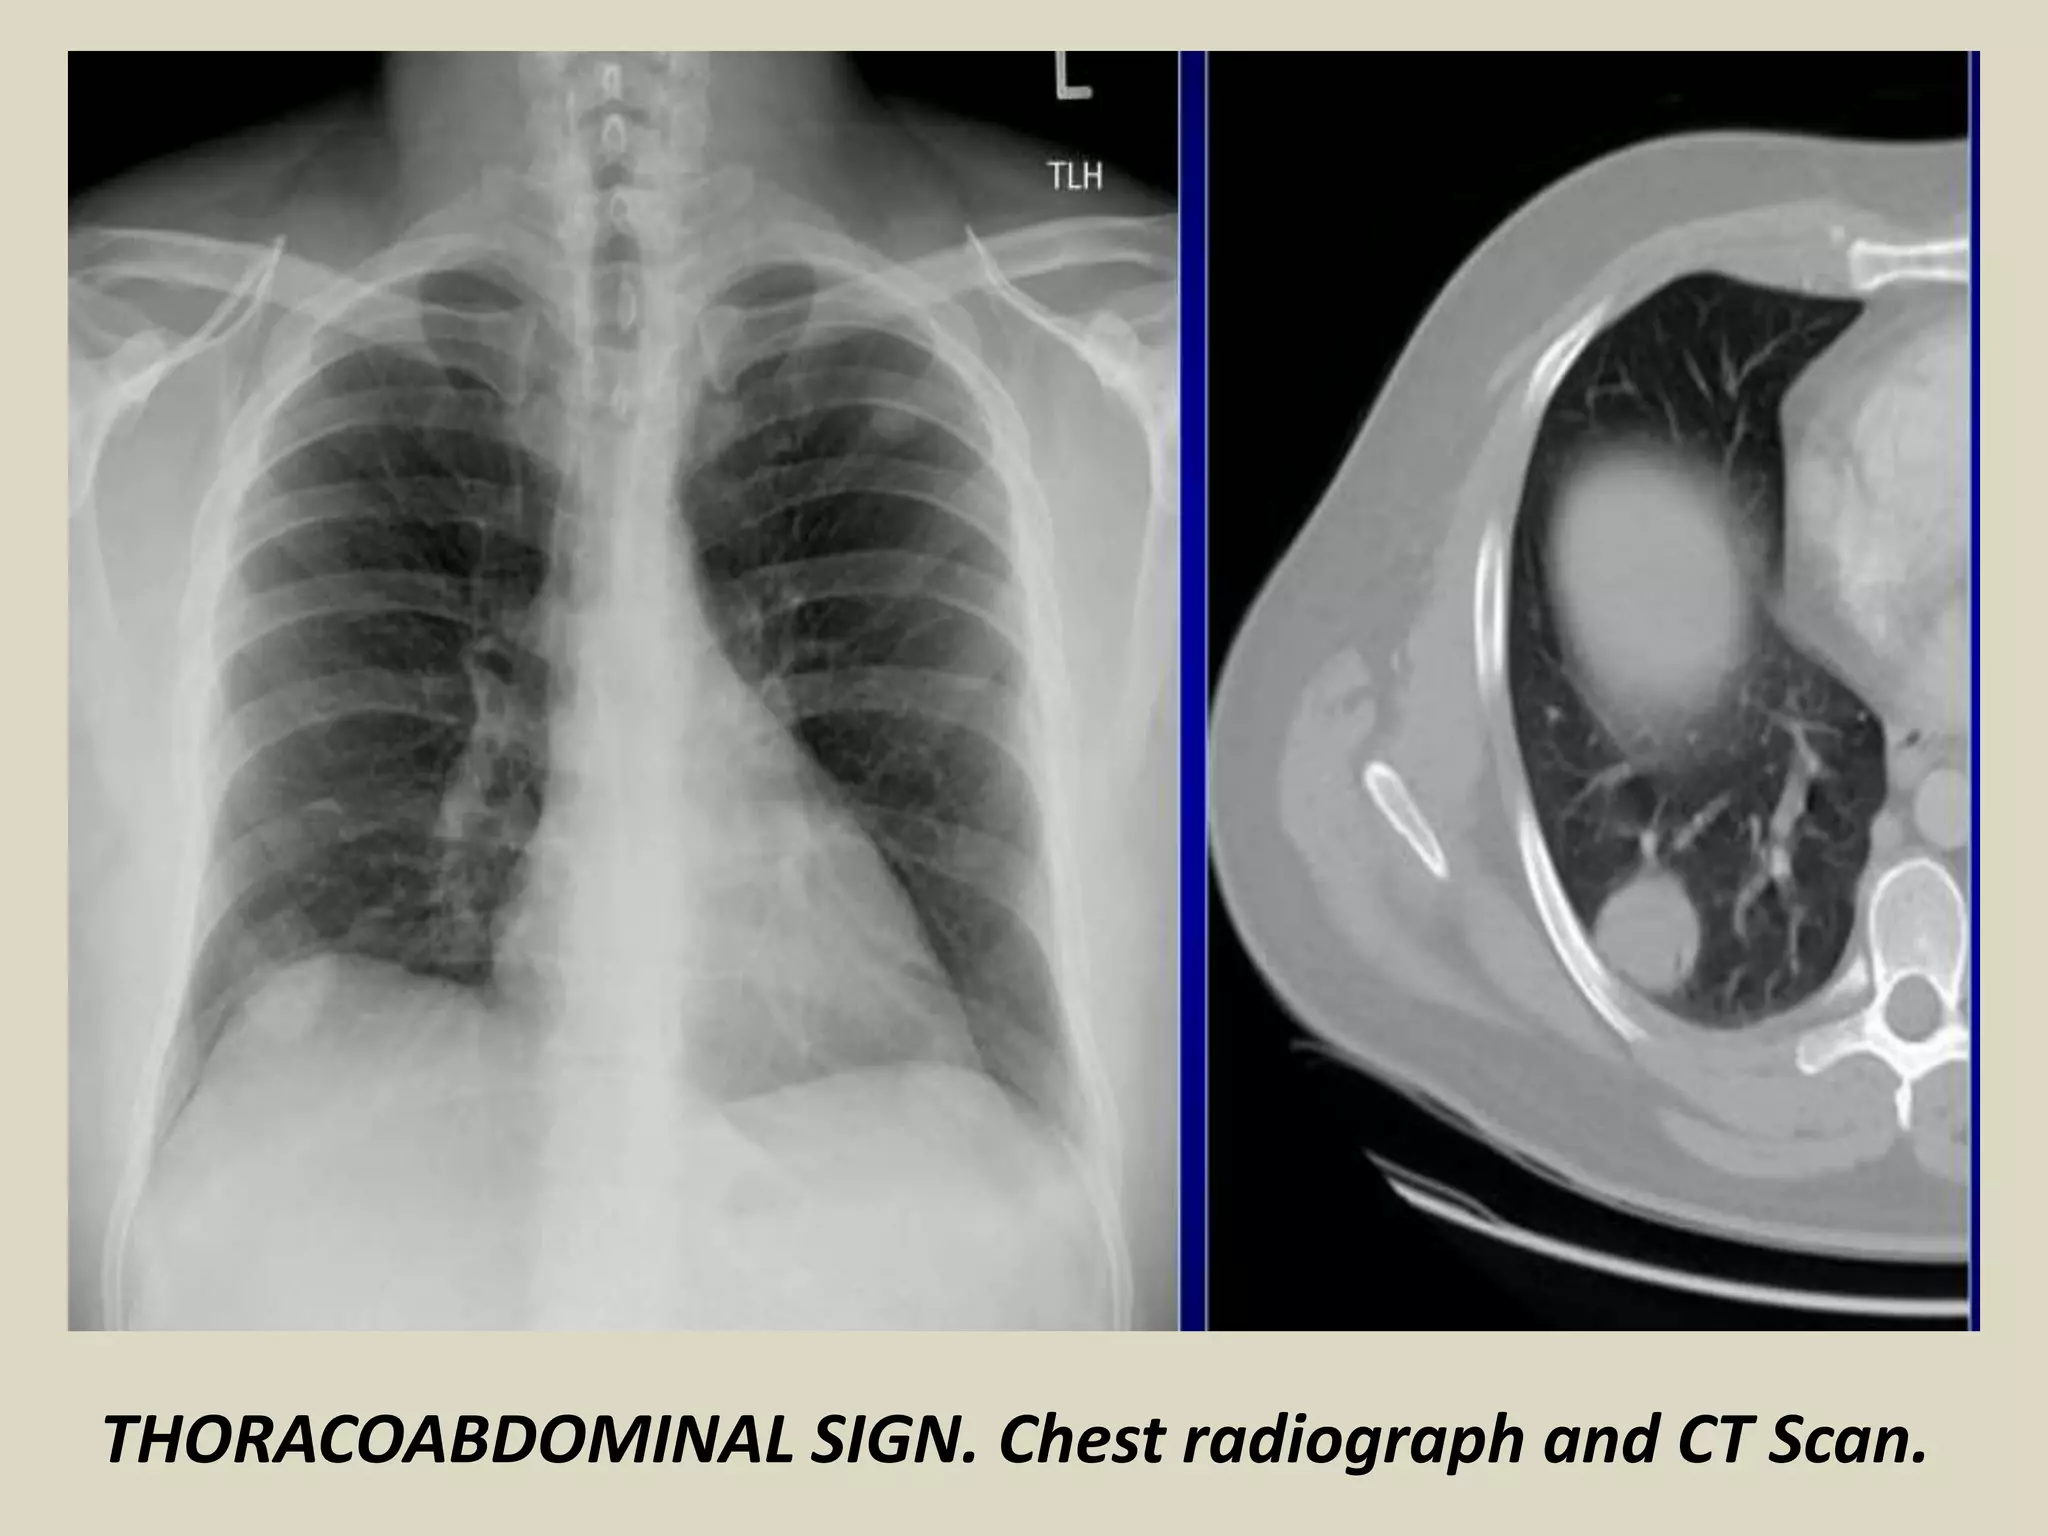

THORACOABDOMINAL SIGN

Posterior costophrenic sulcus extends more caudally than anterior

basilar lung

Lesion extending below the dome of diaphragm must be in posterior

chest whereas lesion terminating at dome must be anterior

Thoracoabdominal signs were described by Felson

THORACOABDOMINAL SIGN. Chest radiograph with schematic drawing. Hamartoma.

THORACOABDOMINAL SIGN. Chest radiograph and CT Scan.

THORACOABDOMINAL SIGN Posterior costophrenicsulcus extends more caudally than anterior basilar lung Lesion extending below the dome of diaphragm must be in posterior chest whereas lesion terminating at dome must be anterior Thoracoabdominal signs were described by Felson THORACOABDOMINAL SIGN. Chest radiograph with schematic drawing. Hamartoma.

THORACOABDOMINAL SIGN. Chestradiograph and CT Scan.